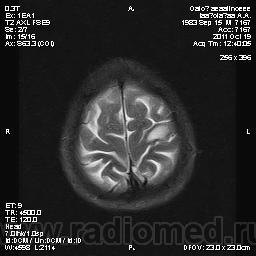

Молодой человек, жалуется только на головные боли и слабость в правой руке и ноге (около месяца).

Пациент полуасоциальный, нельзя исключить анамнез наркоманский....

ППН (включая ячейки пирамидок и сосцевидные отростки) тотально заполнены жидкостным компонентом...

Колеги, спасибо за высказывания. В данном случае про наркоманский анамнез указано не спроста... Есть мнение, что в этом лежит точка отсчета.... По поводу абсцесса и гематомы - не согласен; по поводу первого - нет соответствющей клиники, по поводу второго - не характерна локализация и сигнальные характеристики. Не буду томить общественность касательно собственного мнения. Есть две гипотезы, о которых думается в данном случае: прогрессирующая лейкоэнцефалопатия и новообразование... Но без контраста их не разрешить...